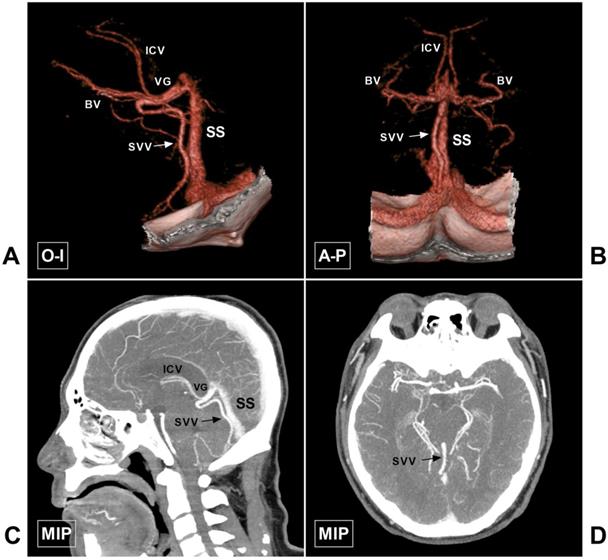

Figure 10

Large SVV. A-B, CTA in O-I and A-P view show a large SVV (arrow), which drains to the VG. C-D, MIP in sagittal and axial view also shows the large SVV (arrow). Abbreviations: A-P, anterior to posterior; BV, basal vein; CTA, computed tomography angiography; ICV, internal cerebral vein; MIP, maximum intensity projection; O-I, outside to inside; SS, straight sinus; SVV, superior vermin vein; VG, vein of Galen.

Discussion

The CDV system mainly refers to the veins around the VG, including the ICV, BV, and VG, of which the VG is the core. The VG mainly receives blood flow from the bilateral ICVs and BVs and then empties into the SS. In addition, the VG and SS receive blood flow from the superior vermian vein, the superior cerebellar vein, the tectal and pineal veins, and the internal occipital vein [5]. The CDV system is characterized by diverse anatomical variations. However, the ICV, BV, and VG are relatively constant. Some veins can be very slim or even absent, or they can be very large. An illustrative case of the large superior vermian vein is shown in Figure 10.